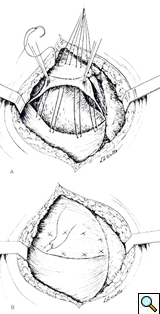

Because of the extreme diaphragmatic elevation an open approach through the chest was selected for correction of the abnormality. After preoperative bowel preparation, the patient was taken to the operating room and a muscle-sparing left antero-lateral thoracotomy was performed in the 5th intercostal space. With this approach the free edge of the latissimus dorsi is mobilized posteriorly and the serratus anterior is freed up at the level of its anterior insertion on the chest wall, allowing easier access to the anterior portion of the diaphragmatic leaflet. The diaphragm appeared morphologically normal but relaxed (Figure 3).

The left dome was opened anteriorly and towards the periphery following the line of insertion into the chest wall, in order to avoid injury to the major branches of the phrenic nerve. The transverse colon and the spleen were displaced inferiorly through the opened diaphragm. The colon was massively distended and was carefully reduced into the abdominal cavity. The redundancy of diaphragmatic dome was such that the posterior edge had to be trimmed removing an elliptical segment of muscle of 14 x 8 cm in size. The diaphragm was reconstructed overlapping the two edges of the opened muscle with interrupted, size O, nonabsorbable U-shaped sutures in a “double-breasted” reconstruction technique, reinforced by a second running layer (Figure 4).

The repair is most easily performed through the chest, with a lateral thoracotomy at the 7th or 8th intercostal space [4]. The strategy of surgical repair has to be adapted to each specific case. The approach through the chest makes the correction of the diaphragm technically easier. It provides exposure over the convexity of the diaphragmatic dome and allows a more precise estimation of the tension that is needed to obtain an optimal correction. The goal of surgical correction is to place the diaphragmatic leaflet in a position of maximum inspiration which relieves compression on the lung parenchyma and allows its re-expansion [4, 10, 11]. The repair of the diaphragm is accomplished by plication of the diaphragm or by imbrication. Imbrication is performed by opening the diaphragmatic dome and overlapping the two edges of the muscle (Figure 4). When the diaphragm is substantially elevated, resection of a portion of diaphragm is required, followed by reconstruction with a double breasted suturing technique.